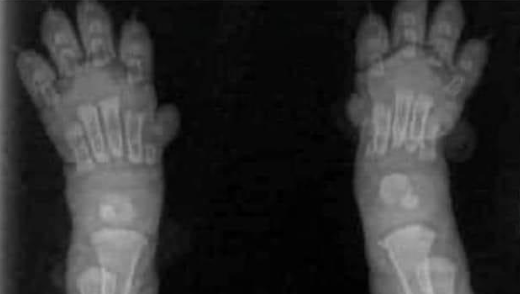

LE SQUELETTE DE VOTRE CHIOT

Votre chiot Berger Allemand a 2 mois, il va grandir jusqu'à 15 mois. Il faut avoir en tête ces photos de radios, afin de comprendre, qu'il est important de prendre soin de lui, de sa croissance jusqu'à la fin de la formation de son squelette.

Radio patte arrière Radio pattes avant

Nous avons spécialement choisi des reproducteurs indemnes de dysplasie sur plusieurs générations, ils sont nourris, avec des croquettes protéinées, et complémentés en viande rouge et ou viande crue, poulet cuit, sardines. On s'attache beaucoup à leur santé, leur apport en bons nutriments. On fait donc tout pour que votre chiot soit issu de géniteurs en bonne santé.